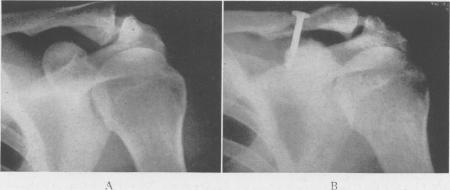

Acromioclavicular Dislocation: End-Results of Screw Suspension Treatment.

Ann Surg. 1948 Jan;127(1):98-111. doi: 10.1097/00000658-194801000-00009.